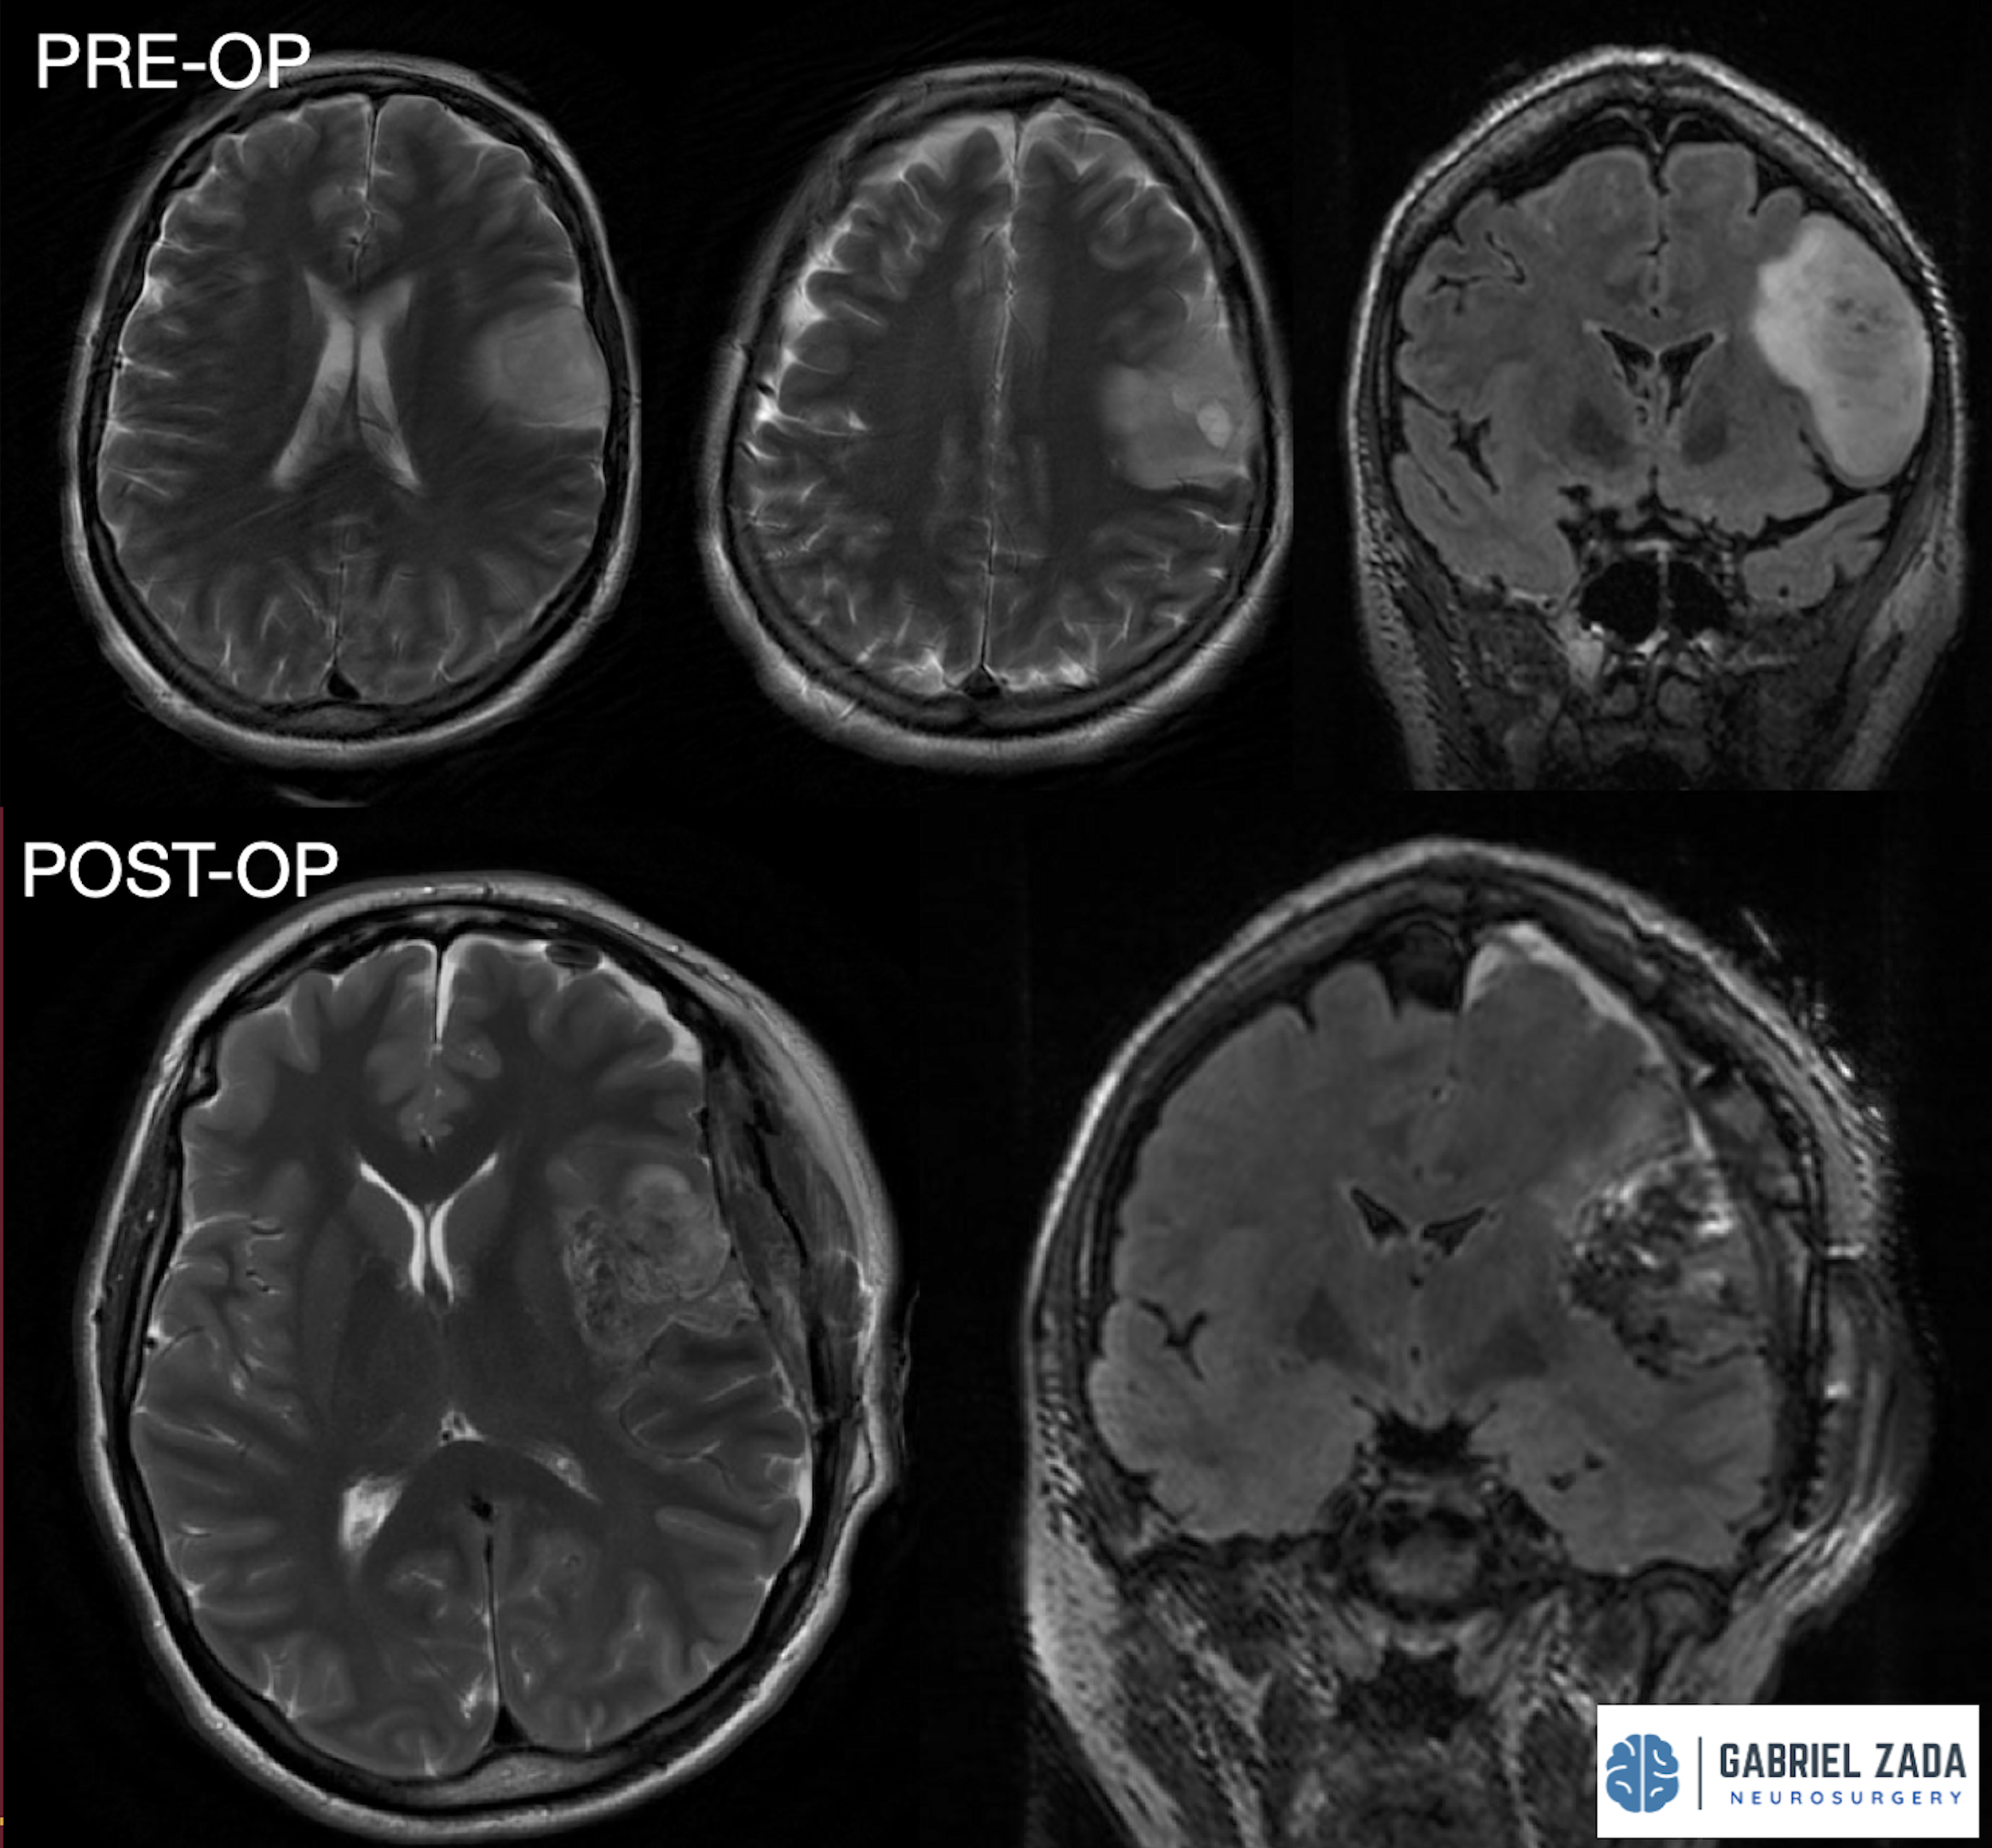

Explore this comprehensive gallery featuring pre‑ and post‑operative imaging of patients with skull‑base tumors treated by Gabriel Zada, MD, MS, FAANS, FACS. These cases highlight Dr. Zada’s expertise in advanced neurosurgical techniques and outcomes.

*Representative cases shown for educational purposes. All images de-identified. Individual results vary.